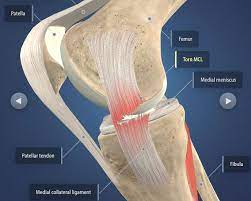

Tenderness along the joint line 3. The main risks with acl knee surgery are: See full list on practicalpainmanagement.com As you can see, these problems often stem from problems with the rehab programme, either from a poorly designed programme or poor patient compliance. An acl injury is a serious health issue and a common injury that requires surgery.

It is important when resting with your leg elevated not to have anything underneath your knee as you want to be stretching it out 5. Phase three on the acl surgery recovery timeline is when the knee is most vulnerable. This is taken either from your own tissue (autograft), or from donor tissue (allograft). People usually recover really well after acl surgery, but many report a few problems in the early stages. Knee pain some pain after acl surgery is common both at the knee itself and around the new graft area but it is usually quite tolerable. The alternative methods are listed below. Most patients can expect to play sports and exercise at a high level. The main risks with acl knee surgery are: Acl reconstruction knee surgery involves replacing the torn anterior cruciate ligament with a new graft. Numbness numbness around the scars is common due to damage to the small nerves around the knee from the incisions. It typically takes seven to 10 days after the procedure, until the patient is comfortable without the assistance of a crutch. See full list on practicalpainmanagement.com Discomfort while walking the diagnosis of an acl injury can be confirmed by physical examination, which includes comparing the injured to the uninjured knee to help determine the state of the acl.